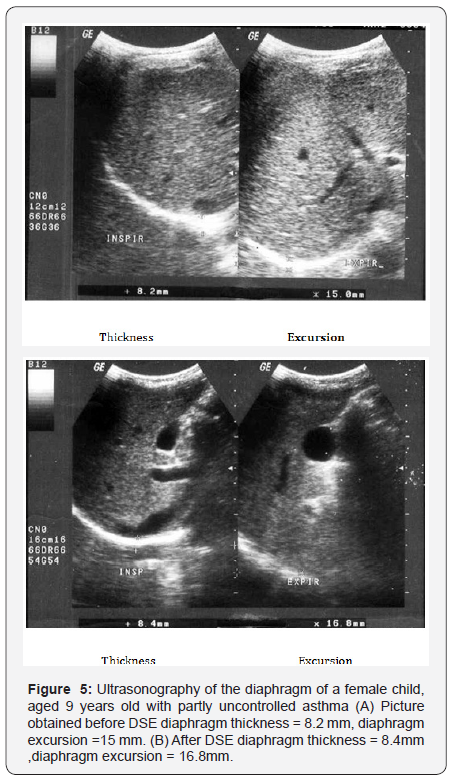

sEMG recording parameters of diaphragm, including amplitude and frequency, were significantly decreased after maximum voluntary ventilation maneuvers (decrease of 18% and 12% from baseline, respectively), P<0.05 (Table 6). After Diaphragm strengthening exercise (DSE), a statistical significant higher values of FEV1, FVC, FEV/FVC, PEF, FEF25-75% and MVV were detected compared to pre-exercise levels (Table 7). There was an increase in both thickness and excursion after Diaphragm strengthening exercise in asthmatic patients (Table 8 and Figure 5).

This study explored the effect of 12 weeks of strengthening exercise of diaphragm in asthmatic children. It revealed a statistical significant higher values of FEV1, FEV1/FVC, PEF and MVV and also a significant increase in diaphragmatic thickness and excursion in asthmatic patients after diaphragm strengthening exercise. Many authors studied the effect of non respiratory exercise on pulmonary function parameters in asthmatic children [19, 21,26-29,] Their results revealed marked improvement in pulmonary functions after diaphragmatic training. Girodo [29] studied the effect of 16-week program of diaphragmatic strengthening exercise for asthmatic patients. They found a significant reduction in medication use and in the intensity of asthmatic symptoms. A follow up at two months found that many patients have returned to earlier medication levels with marked impairment in their PEF. McCool [30] postulated that weight-bearing maneuvers may be used to strengthen the diaphragm and expiratory muscles. However they found that although strength training leads to myofiber hypertrophy, it does not result in mitochondrial proliferation, so weight lifting increases diaphragm structure and pressures with less effect on contractility and excursion.